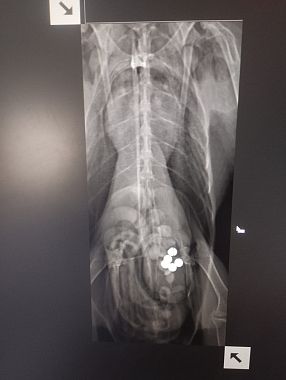

Dagli accertamenti veterinari è emerso che l’Avocetta ha lo stomaco pieno di pallini di piombo, ingeriti con ogni probabilità in modo accidentale mentre si alimentava sul fondo di una zona paludosa, suo habitat naturale. Durante la digestione, il piombo rilascia sostanze tossiche che provocano una grave intossicazione, debilitano l’animale e possono portarlo alla morte nel giro di pochi giorni.

"Se le condizioni lo permetteranno, nei prossimi giorni verrà effettuata anche una lavanda gastrica per rimuovere direttamente i pallini ancora presenti nello stomaco. In alternativa, si spera che l’animale riesca a espellerli naturalmente, evitando un’ulteriore assimilazione del metallo. - prosegue la nota - Il recupero sarà comunque lungo e delicato. Il piombo infatti permane a lungo nell’organismo e può causare ricadute gravi, compromettere la capacità di volo e di alimentazione autonoma".